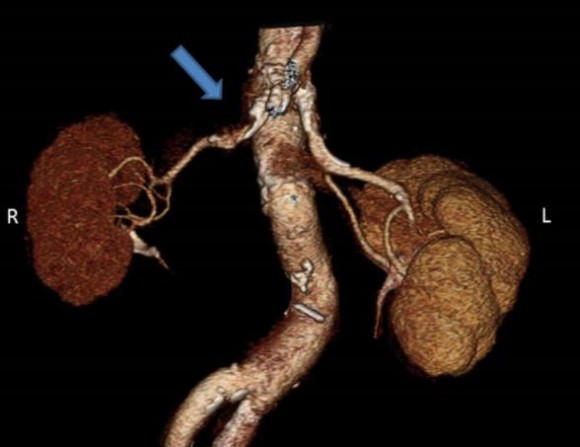

신장은 위 그림과 같이 혈관 덩어리로 되어 있다. 양쪽 신장에서는 심장에서 보내는 피의 1/4로 70kg인 사람을 예로 들면 1분에 1.2L의 피를 받고 있다.신장에서는 피에서 노폐물을 제거하기 위해 항상 일정한 혈압을 유지해야 한다. 만약 출혈이 심하고 피가 부족해 신장에 피가 나오지 않게 되면 소변이 나오지 않게 되고, 길어지면 신장 기능이 마비된다.

CT 검사에서 오른쪽 신장이 작아져 있고 그쪽으로 가는 동맥이 좁아져 있는 것이 관찰된다.그런데 고혈압 중 신장 때문에 2차적으로 혈압이 오르는 병이 있다. 즉 위 사진처럼 신장에 가느다란 동맥이 좁아져 생기는 고혈압을 말한다. 이런 병은 전체 고혈압의 5% 정도로 많다는 연구 결과도 있다. 이를 신장혈관성고혈압(renovascular hypertension)이라고 한다.

위 사진처럼 신장으로 가는 동맥이 7585%가 막혀야 고혈압이 생기고 60%까지는 증상이 없다. 만일 이 질환이 빨리 발견되면 이 혈관을 수술로 확장시켜 완쾌할 수도 있기 때문에 중요한 병이다.